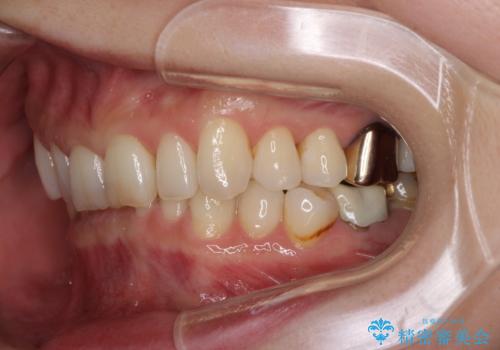

その後、オールセラミッククラウンにて補綴治療を行う予定でしたが、処置した歯以外にも治療が必要と思われる歯があったり、デコボコした歯列も気になるとのことで、患者様希望によりインビザラインにてマウスピース矯正を行うこととしました。

まずは矯正治療前に必要なむし歯処置を行い、その後矯正治療を行ってから、最後にオールセラミッククラウンなどで補綴治療を行うこととしました。

咬合力が非常に強く、全体的に歯が擦り減っている状態であったので、理想的な咬み合わせを達成することは難しく、また咬合力が強い方のマウスピース矯正は、思い通りに動かないことがあるため、ワイヤー矯正の方が望ましいように思えました。

治療途中で2年強、体調を崩されて通院ができなくなってしまったため、必ず通院が必要なワイヤー矯正ではなく、マウスピース矯正で結果的には無事に治療を終えることができました。